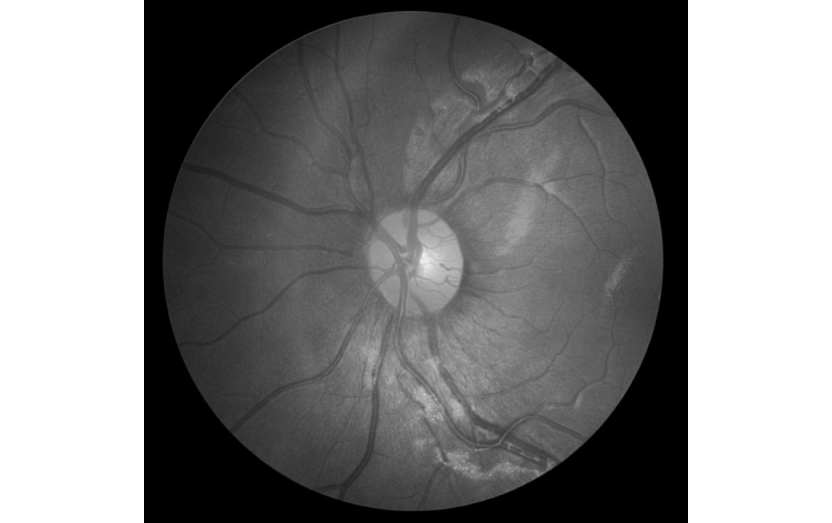

Our case At , we have been running consulting business for over 5 years. We focus on helping other companies to leverage AI to optimise their operations. Vast majority of our projects are in a space of computer vision. DeepSystems Whenever we start negotiating Scope Of Works and pricing, it’s very beneficial to have some early, dirty and working prototype. Otherwise, it’s hard to estimate the efforts and put appropriate price. So in our business practice it’s quite usual to build something before the contract even signed. But in this post, we suggest to focus less on us and more on you guys. Your case Suppose you have an idea (or business request) to solve semantic segmentation or object detection task that attacks a particular business need. It might be finding cracks on the road, vessels on an eye, detecting persons in the crowd or something else. Person detection Quality inspection: finding cracks on a road Eye vessels automatic segmentation How much time will it take you to go from an idea /business request to something working? Definitely, the answer depends on the background. Let’s consider the following categories of people. . Uses Python as a main language, has experience with TensorFlow, PyTorch. Has math, statistics and machine learning background. Category 1. Data scientist . Uses C++ as a main language, also familiar with Docker, RabbitMQ, SQL & NoSQL databases. Has computer science degree. Category 2. Software developer . Responsible for safety, quality, efficiency, and cost reduction, for instance, in manufacturing, agriculture or construction. Or, in medical domain, we might consider a doctor as an example. Category 3. Domain expert To make things interesting, let’s put to perform the task. 1 day limit Our empirical answer is that, on average, only a “Data scientist” has chances to have the job done within given time constraints. And, actually, not every data scientist — he needs to have experience in computer vision, as well as solving similar tasks in the past. The main reason our “ideal data scientist” have chances is that he has working pipeline (or at least, good understanding of it) to address these kinds of tasks. So he knows: what software to use to label the data And he has: code / library to construct training data from labeled images, for example, by augmenting the labeled images Pytorch / tensorflow implementations of Deep Learning models like Unet, Mask R-CNN or others, which he used in his projects in the past Visualization tools to present the solution In other words, our data scientist leverages his experience and ecosystem to get the result in a short time period. But what about 2 other categories of people? The time limit is too tough for them. In most cases, they have no idea how to approach the task. AI is not only for data scientists, everyone should use it Actually, are very familiar with various development tools and transition to Data Science is the most natural for them. After taking several online courses, some kaggle competitions and working on personal projects they are in a very good shape. But the transition process is still hard, it takes time and motivation. software Developers As for , they are in the worst situation — most of them have neither computer science nor data science background. But nevertheless, these guys are very powerful in a way that they are the only ones who face real needs of people / businesses on a daily basis. People involved in medicine, agriculture, construction, production pipelines see inefficiencies, they understand the real pain, or, speaking in other words, real tasks to solve. So the ideas coming from these guys are extremely valuable. domain experts A following questions arise: “Is that situation normal?”, “Maybe, everyone should mind his own business?”, “Let software engineers develop software, and construction guys construct the bridges the way they used to?” Our answer is that AI today has so much to offer and it’s not very clever to ignore it. Literally, every industry will benefit from AI and, as a result, we will live longer and happier. Going back to our topic, let’s make the following statement: “We believe that Data Scientists, Software Engineers and Domain Experts should be able to leverage AI today, right now.” And one more statement: “ ” It should take 2 hours to go from idea to “dirty prototype” for all 3 category of people We know that it is possible for computer vision applications — recall our earlier discussion on DeepSystems’ policy to build a prototype before signing a contract. Obviously, we can do that not for every task, but for the most common tasks in computer vision like detection or segmentation — we can and actually do. Supervisely platform — steps toward AI democratisation We leverage our platform not only to prototype fast but also to perform active learning and continuously improve the quality of models. Supervise.ly The idea behind the platform is to address the entire pipeline — from data labelling to training and running neural networks within a single environment. Community edition of Supervise.ly is free, available online, and, mostly, open sourced. The easiest way to start is to watch the following video: It covers 3 main concepts we have to deal with when building an AI app: Data labeling Data preparation Model building More importantly, the entire process of building a prototype is shown there — semantic segmentation model is built to distinguish lemons from kiwi. You will find all information to reproduce experiments described in the video. here After watching, we hope that you realise that building AI models today is actually easy and you can start doing it straight away (though, several years ago it was not the case). We will keep releasing new videos on weekly basis to attract more people to AI development. Let me put a disclaimer here. We think that deep understanding of AI technologies is beneficial and worth the efforts. For instance, in you will find great guidelines on how to better approach AI field. this blog post If you found this article interesting, then let’s help others too. More people will see it if you give it some 👏.